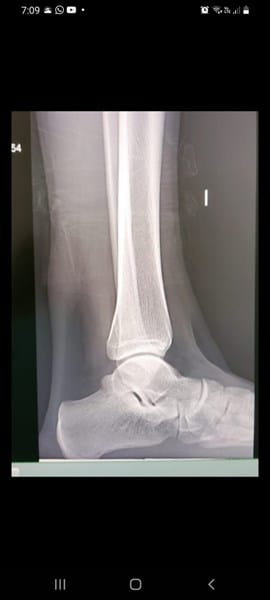

EndocrinologíaBiologíaHuesos y articulaciones manuel jose uribe pozo el 10 dic. 21 Puedo crecer 1 o 2 cm a mis 18 años recién cumplidos TENGO ESTAS RADIOGRAFÍAS QUISIERA SABER SI PUEDO CRECER 1 O 2 CM@ Seguir Siguiendo Dejar de seguir